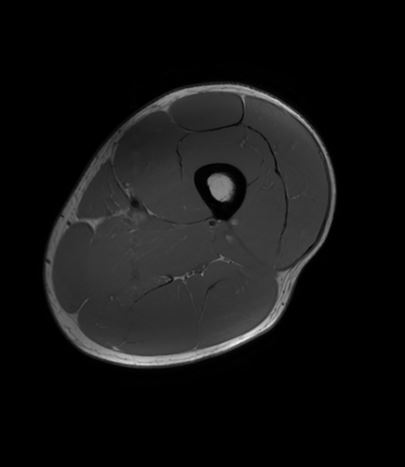

En MR-scanning af hofte eller bækken er en skånsom, smertefri undersøgelse, der giver meget detaljerede billeder af området.

Vores 3 tesla MR-scanner bruger et kraftigt magnetfelt og radiobølger til at skabe præcise billeder af muskler, sener, knogler, brusk, ledkapsler og omkringliggende bløddele – helt uden brug af røntgenstråling.

MR-scanning er særligt velegnet til at undersøge komplekse strukturer som hofteleddet og bækkenet, da den viser detaljer, som ikke kan ses med andre undersøgelsesmetoder som røntgen. Dette giver mulighed for at stille en præcis diagnose og planlægge den rette behandling for dine smerter.

Eksempler på MR Scanninger